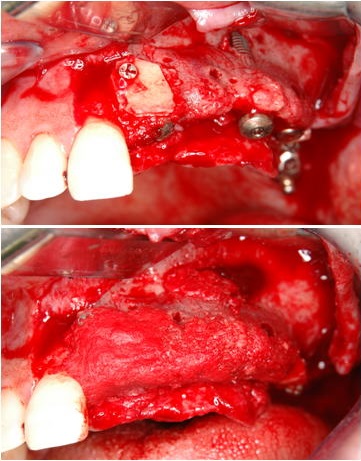

3.極度の骨・軟組織欠損がある2歯欠損症例(症例 5、自家骨移植と有茎口蓋弁移植)

極度の骨欠損があったが、オトガイ部から10mmの厚みの皮質海綿ブロック骨移植にて審美的インプラント治療を行いました。歯肉の厚みを増やすために有茎口蓋弁移植も併用しました。

4.極度の骨・軟組織欠損がある2歯欠損症例

(他院でトラブルとなった症例 2の再インプラント治療、自家骨移植と有茎口蓋弁移植)

まず予後不良インプラント撤去し、極度の骨欠損があったが、オトガイ部から10mmの厚みの皮質海綿ブロック骨移植にて審美的インプラント治療を行いました。歯肉の厚みを増やすために有茎口蓋弁移植も併用しました。